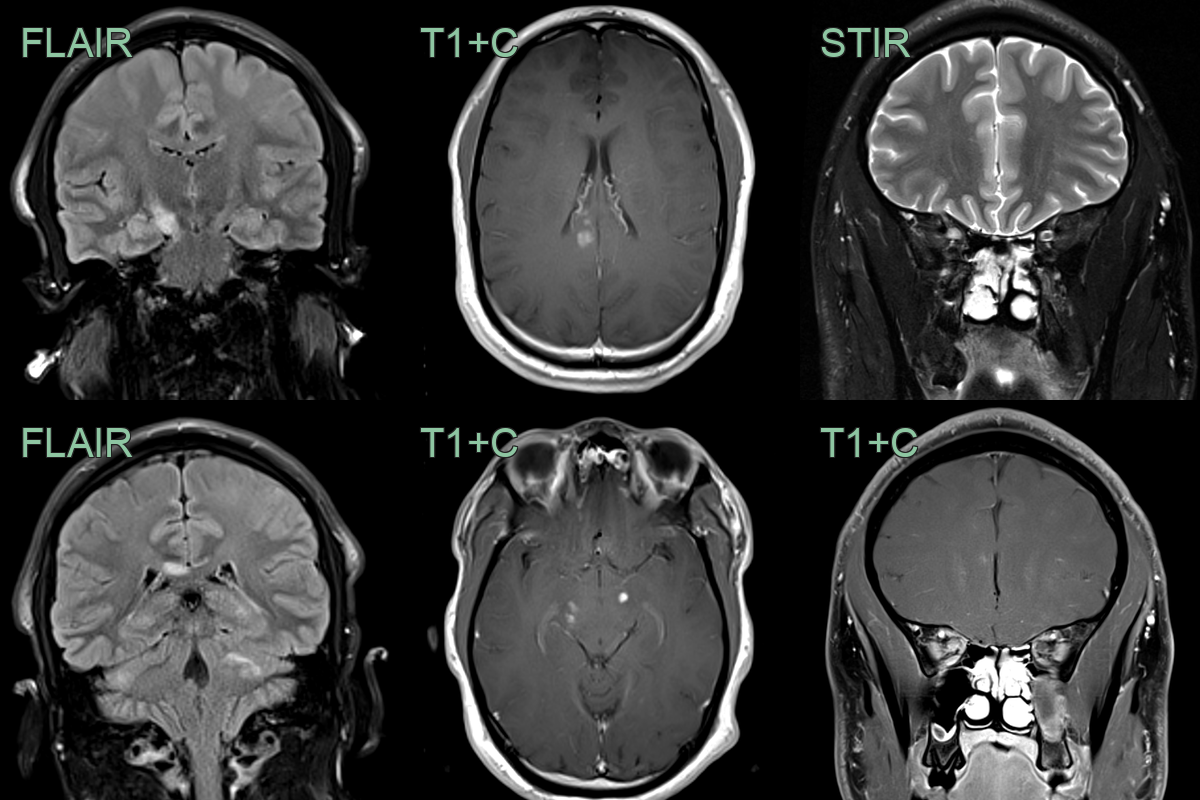

- A 40 year old presented with confusion and upper and lower limb weakness and sensory disturbance.

- MRI showed extensive white matter lesions within both cerebral hemispheres associated with diffusion restriction and peripheral enhancement.

- In the cord, there were multiple swollen mainly central short segment cord lesions.